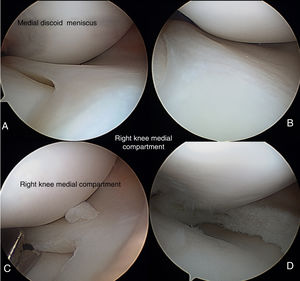

The patient was recommended physiotherapy and to limit his sporting activities, but the pain persisted and he went for a check-up after 11 months with further symptoms in the right knee. Due to non-improvement after one year of modifying his sports activity and treatment of symptoms, it was decided to perform arthroscopy of the right knee, where the following was found: synovial tear, cartilage without changes, complete medial discoid meniscus according the Watanabe9 classification, no rupture, and occupation of the whole medial joint space. Medial meniscus remodelling was performed until a normal meniscus shape was achieved, approximately 1cm from capsular insertion up to the new free edge (Fig. 2).